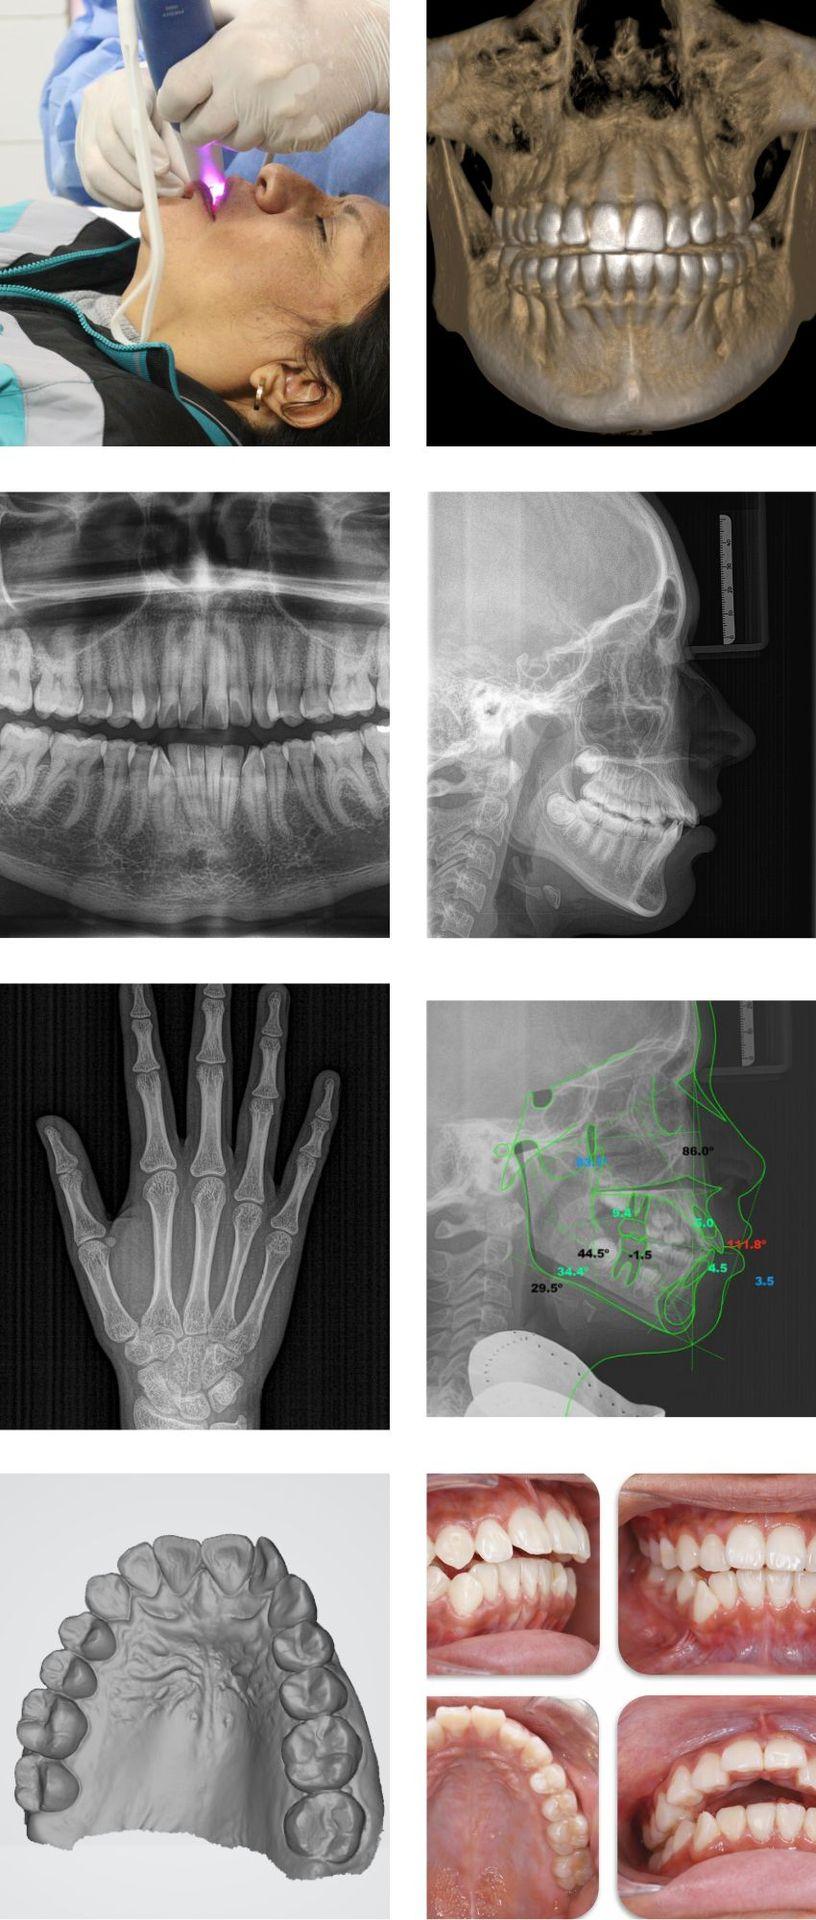

PAQUETE ORTODÓNCICO

Conjunto de estudios radiológicos especializados que permiten una evaluación precisa de la posición dental y ósea, fundamentales para la correcta planificación de tratamientos de ortodoncia.

- RX PANORÁMICA

- RX CEFALOMÉTRICA

- FOTOS CLÍNICAS (INTRAORALES/EXTRAORALES)

- 2 ANÁLISIS CEFALOMÉTRICOS

PAQUETE ODONTOPEDIATRÍCO

Pensando en la salud bucal de los más pequeños, ofrecemos un paquete completo para el cuidado y prevención dental infantil.

- RX CARPAL

PAQUETE 3D

Estudio radiológico avanzado que combina tomografía dental 3D (CBCT) y radiografía dental, permitiendo una evaluación precisa de las estructuras óseas y dentales para una planificación ortodóncica segura y detallada.

- TOMOGRAFÍA BIMAXILAR

- 1 CORTE TOMOGRÁFICO (RX PLACA)

PAQUETE DIGITAL ESCÁNER

Servicio de diagnóstico digital avanzado que integra tomografía dental 3D (CBCT) y escáner dental, proporcionando imágenes precisas y modelos digitales para una planificación odontológica moderna y eficiente.

- TOMOGRAFÍA CONE BEAM

- ESCÁNER DIGITAL (INTRAORAL)

ANÁLISIS CEFALOMÉTRICOS

Es una herramienta clave para evaluar la relación entre los huesos, dientes y tejidos faciales.

FOTOGRAFÍAS CLÍNICAS

Son fundamentales para documentar el estado bucal del paciente con precisión y detalle. Permiten evaluar estructuras, planificar tratamientos y realizar seguimientos visuales, facilitando una comunicación clara entre especialista y paciente, además de respaldar diagnósticos y resultados clínicos.